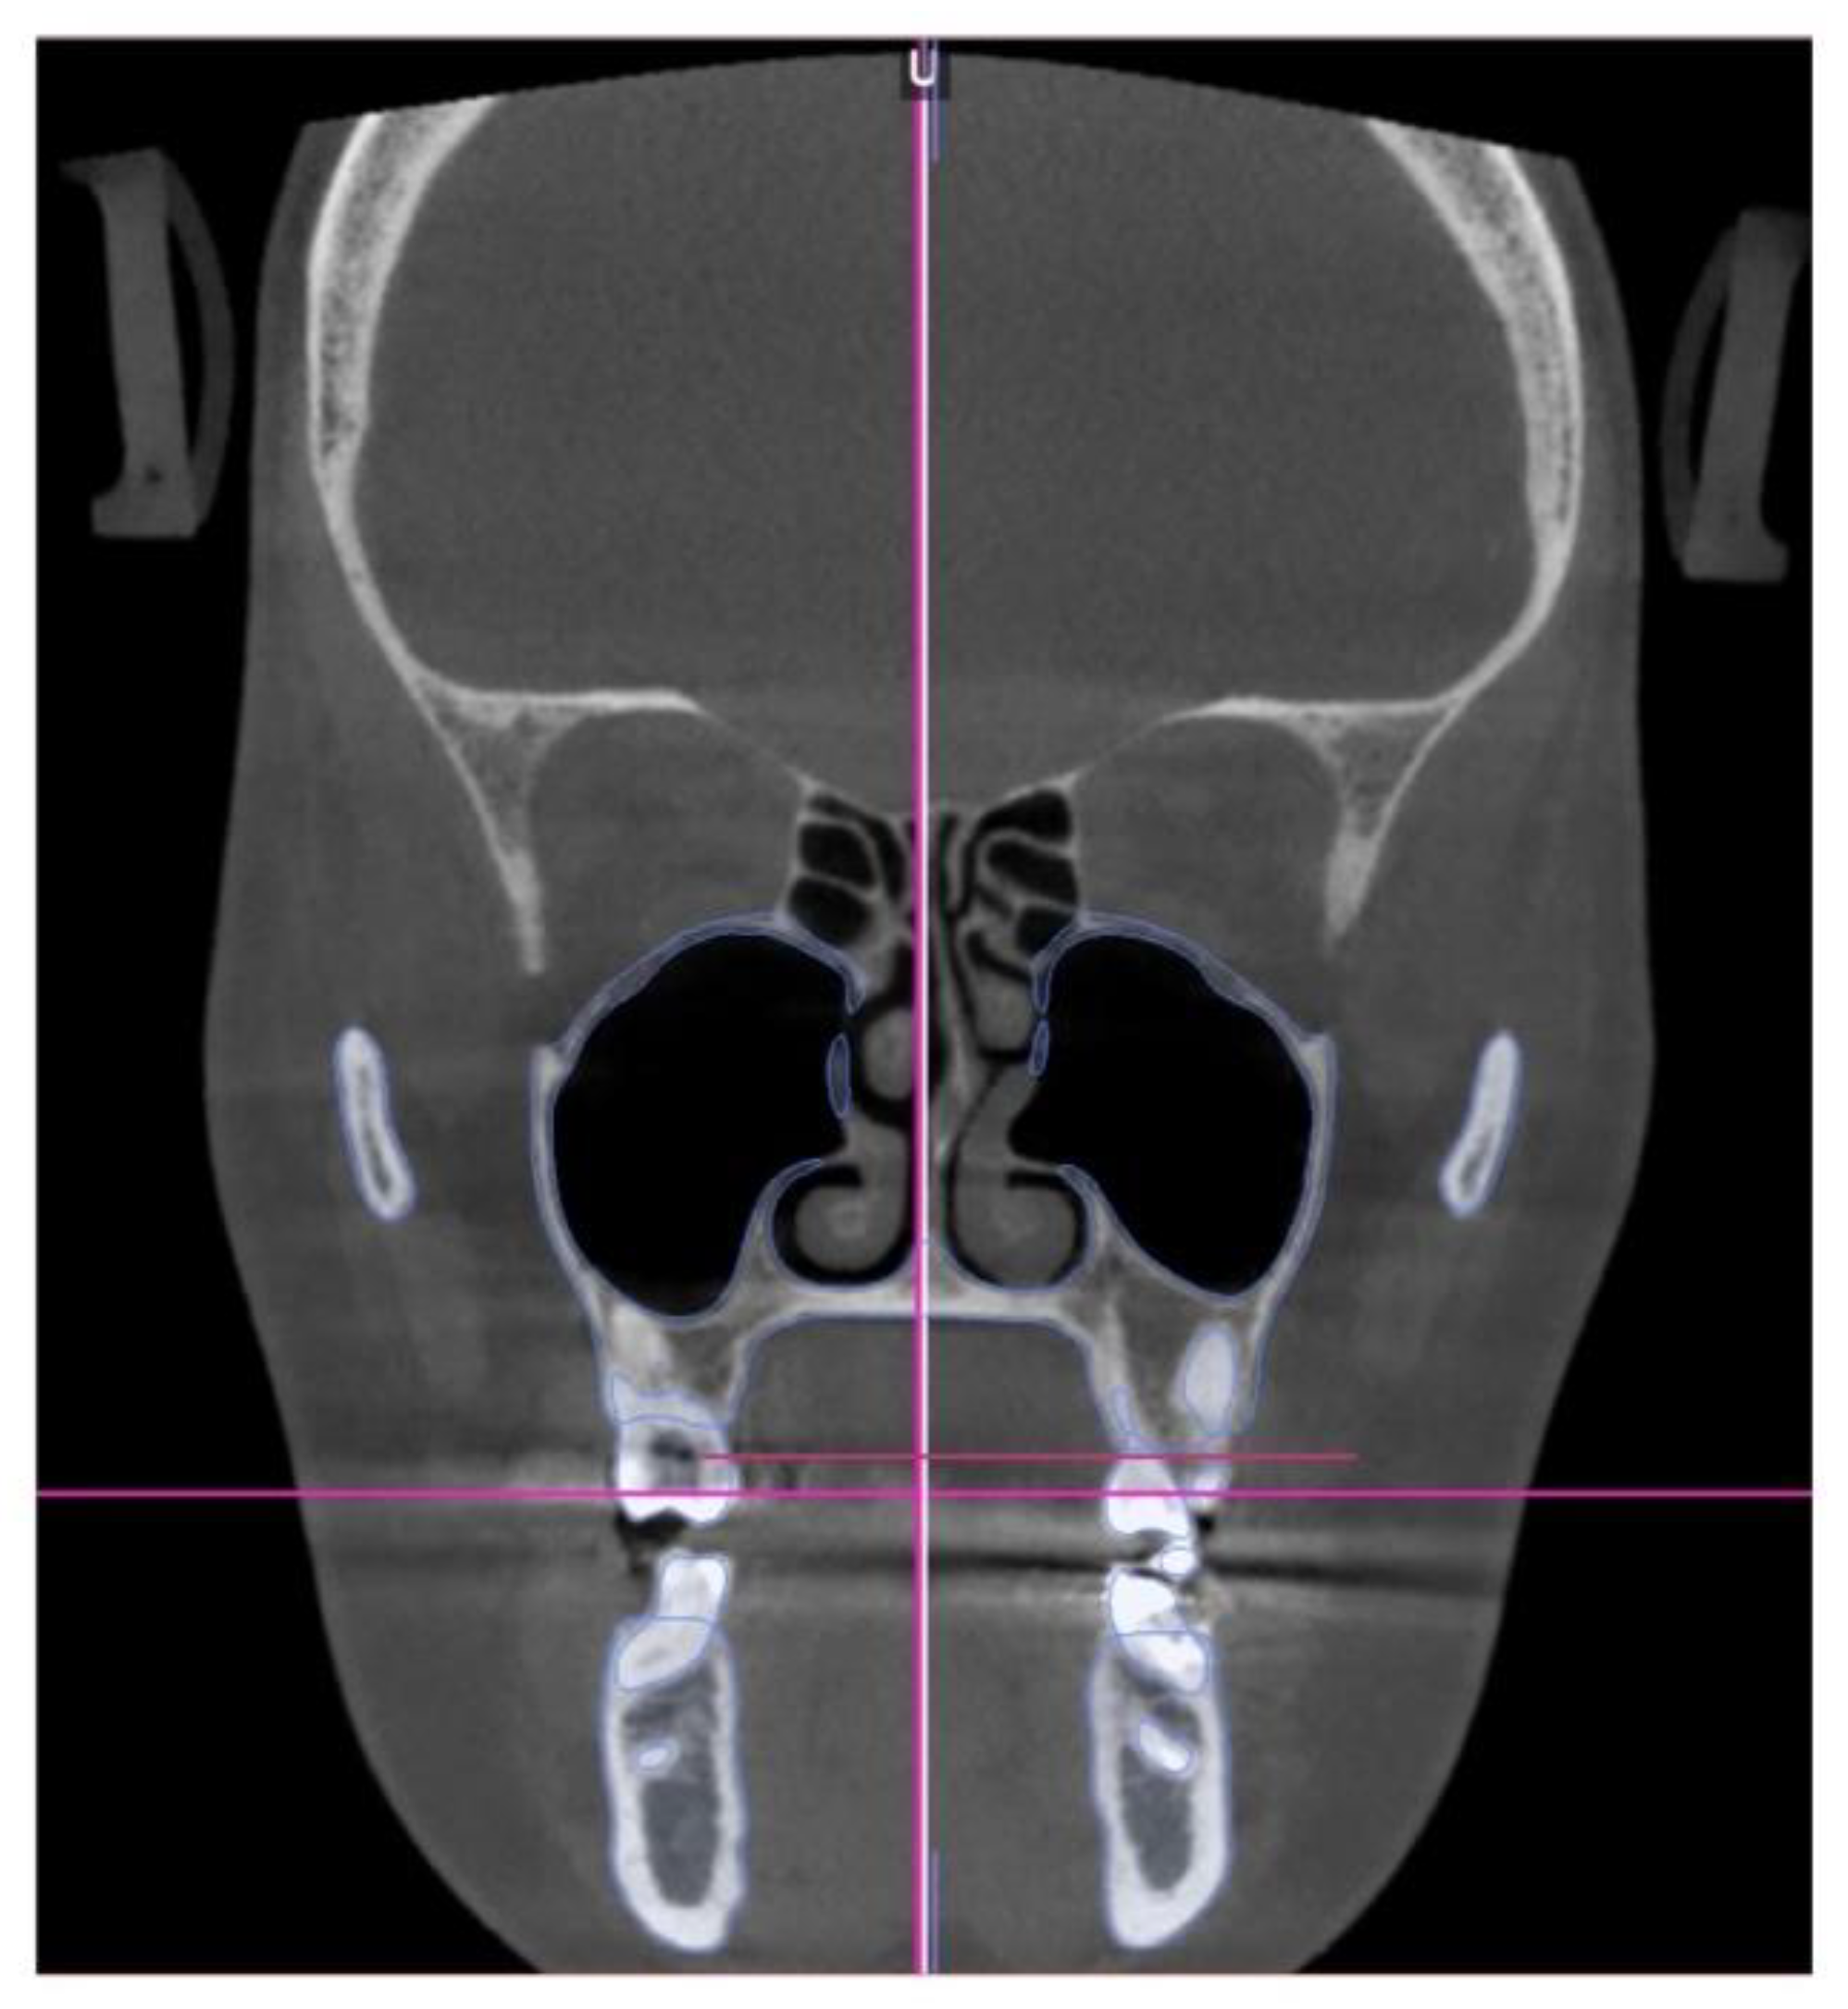

Orbito-Condylion line was used to orient the maxilla-mandibular complex before and after expansion [13] in sagittal plane, Orbital plane was used for the coronal plane orientation, and ANS-PNS plane was used to orient the pre-treatment maxilla-mandibular complex in axial plane. The limitation of the pre-treatment CBCT record was patient not maintaining habitual occlusion. Due to this limitation only maxillary 3D measurements will be compared. (Figure 4)

Figure 7. Pre-treatment coronal plane orientation depicting parallel orientation of the palatal plane relative to the constructed Orbital plane. The vertical dento-alveolar positions of maxillary molars indicate canting of the maxillary occlusal plane. .

Figure 4. Pre-treatment CBCT volume orientation in three planes of space. A, B- orientation in sagittal plane with Orbito-Condylion plane as a reference, C - axial plane orientation with ANS-PNS plane as a reference, and D - coronal plane orientation with Orbital plane as a reference line.

Figure 10. The initial inclination (yaw) of the maxillary base at the level of the posterior wall of the maxillary sinuses and the inferior orbital fissure. Ort—Orbit; IOF—Inferior Orbital Fissure; MxS—Maxillary Sinus; NS—Nasal Septum; NB—Nasal Base.